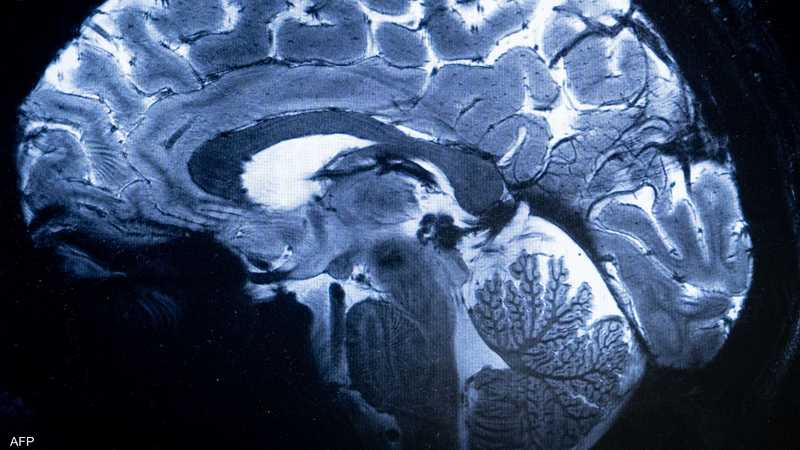

وأظهرت عمليات مسح التصوير بالرنين المغناطيسي لـ30 مريضا أدخلوا المستشفى بسبب “كوفيد 19” في وقت مبكر من الوباء قبل نشر اللقاحات، علامات على التهاب في جذع الدماغ، وهو جزء صغير لكنه بالغ الأهمية لأنه يتحكم بوظائف الجسم التي تدعم الحياة، مثل التنفس والنبض وحركة الدم.

وتشير عمليات المسح إلى أن الإصابات الشديدة بفيروس كورونا يمكن أن تثير رد فعل مناعيا يؤدي إلى التهاب جذع الدماغ، مما يسبب أعراضا يمكن أن تستمر لأشهر بعد خروج المرضى من المستشفى، وذلك حسب الدراسة المنشورة في صحيفة “برين” العلمية.